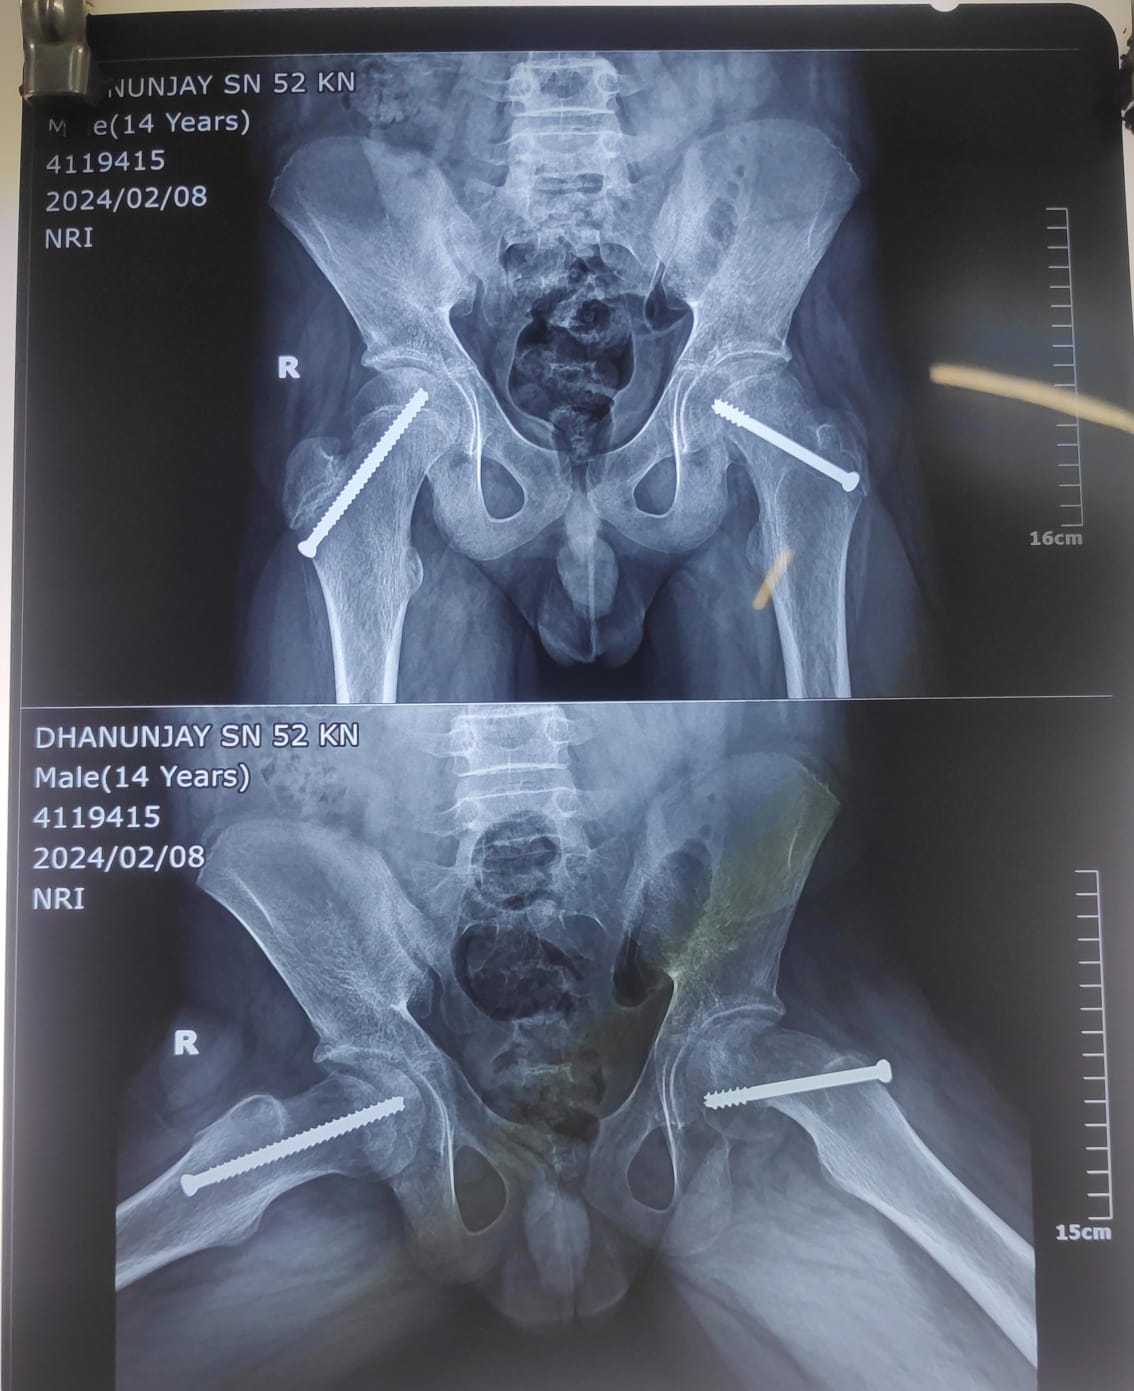

Slipped Capital Femoral Epiphysis (SCFE)

Slipped Capital Femoral Epiphysis

SCFE involves the slippage of the femoral epiphysis, which can lead to altered hip mechanics. Early diagnosis and appropriate management are critical to prevent further damage to the hip joint.